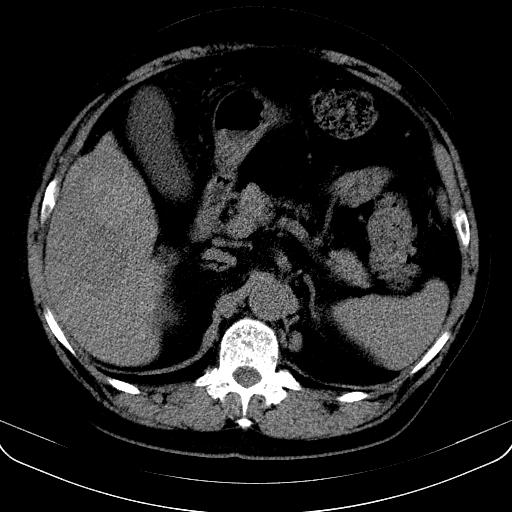

以下是引用jia119在2008-3-5 13:31:00的发言:[br]肝内多发片状低密度影,密度不均,我还是考虑肝ca可能,另肝内小囊肿,胆囊增大。

以下是引用形影不离在2008-3-5 12:18:00的发言:[br]肝硬化伴门脉高压征,肝内占位待排,增强再说.

以下是引用随光逐影在2008-3-5 21:11:00的发言:[br]肝硬化伴门脉高压(食管下段静脉曲张),肝癌不排除。建议:行ct增强扫描检查。

以下是引用同在2008-3-5 13:56:00的发言:[br]考虑肝癌可能性大,胆囊增大.